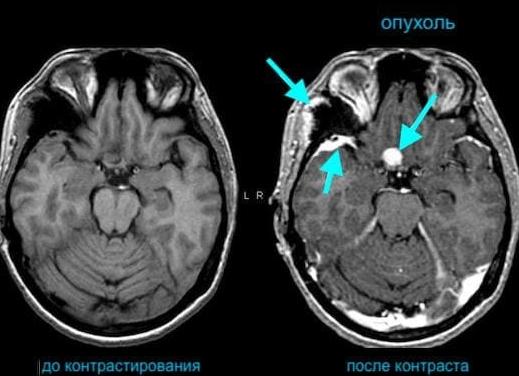

В сравнении с компьютерной томографией без контраста обследования со специальными препаратами помогают сделать более детализированные снимки. Нередко после проведения стандартного (нативного) КТ без контраста пациенту назначают повторное обследование, но уже с введением специальных растворов. Обычно это происходит, когда на снимках видны новообразования или признаки склеротических изменений в тканях.

Важно! Только введение контрастного вещества позволяет установить точные размеры и характеристики патологических очагов — аневризм, опухолей, тромбов и холестериновых отложений.

Особую ценность имеет то, что показывает КТ с применением контраста воспалительные и гнойные процессы, кисты на внутренних органах. Диагностируются с помощью этого метода мальформации сосудов, тромбоз и склероз, патологии аорты (аневризма, расслоение и стеноз). Показано обследование с внутривенным контрастированием и при подозрении на опухоли в костях, тканях мозга, внутренних органах, лимфатической системе.

На снимке области накопления контраста высвечивается белым цветом, что дает возможность четко увидеть отдельные секторы исследуемой зоны, поставить правильный диагноз.